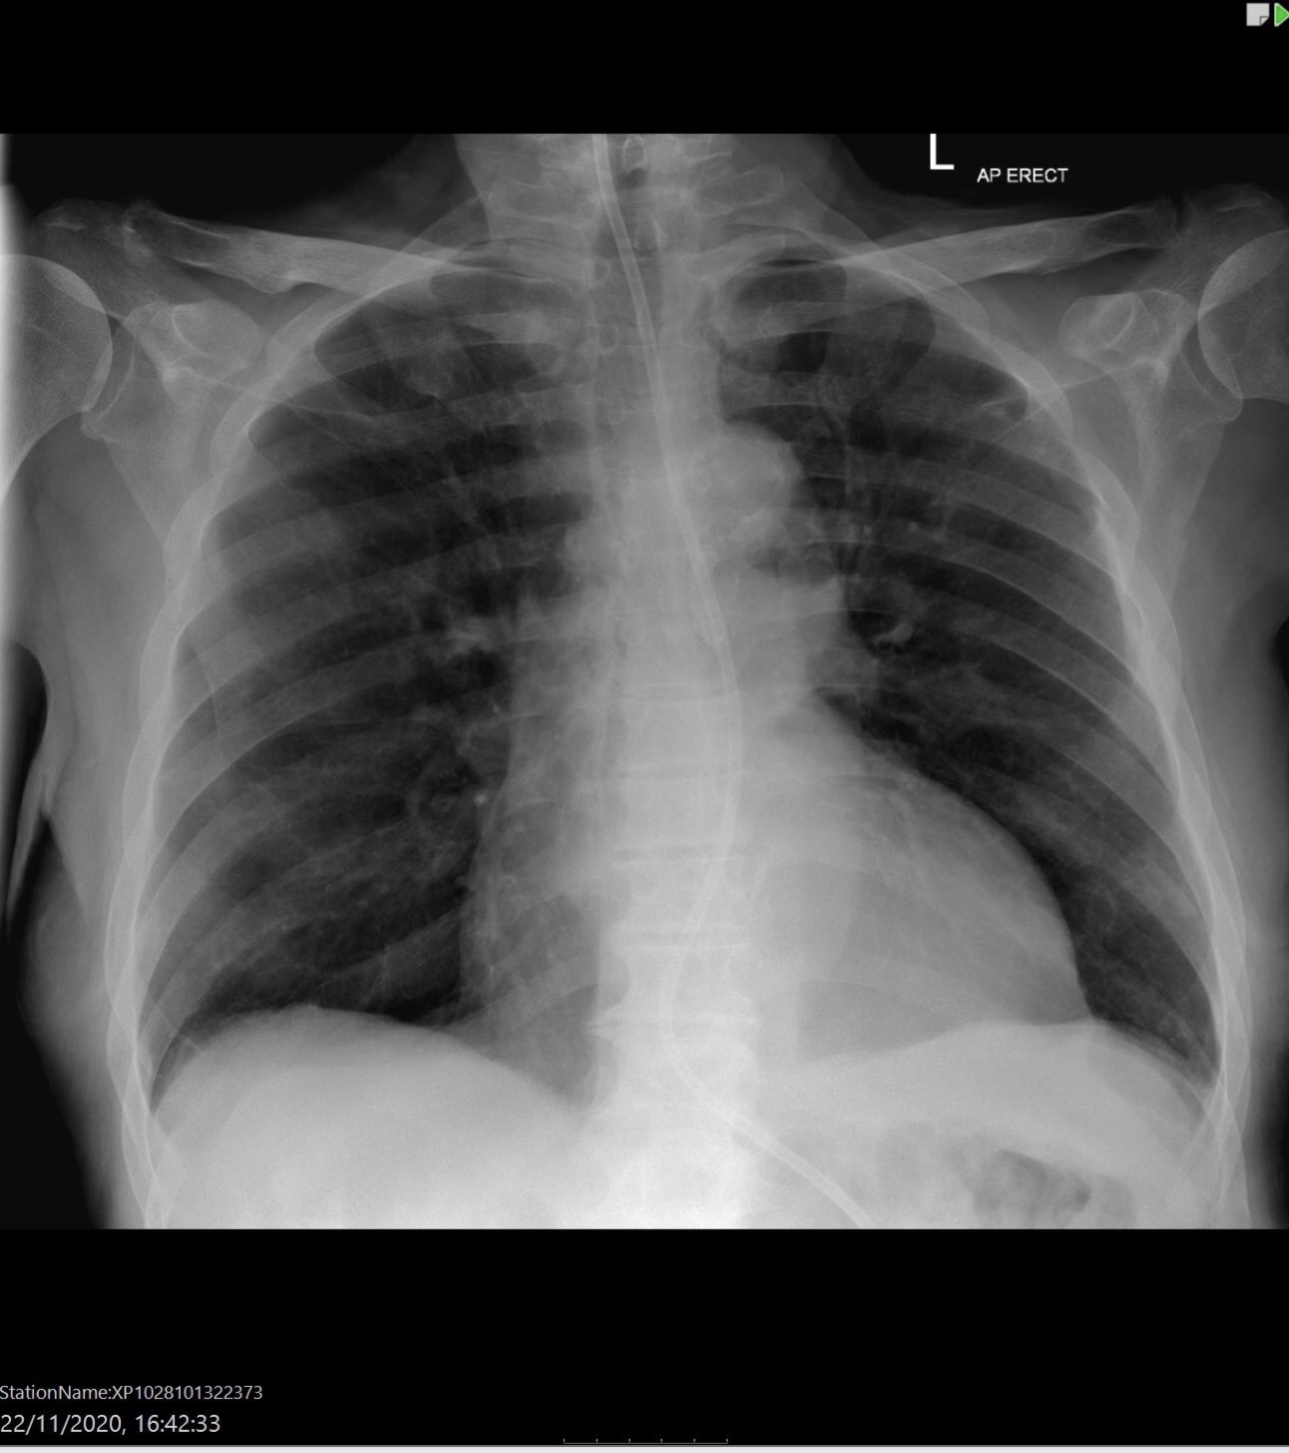

Left sided pneumothorax

Heart failure

Alveolar oedema

Kerley B lines

Cardiomegaly

Dilated upper lobe vessels